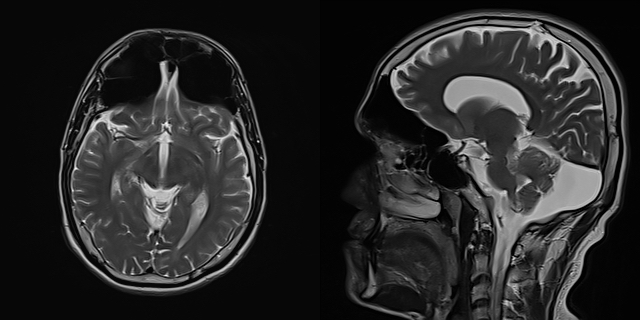

Magnetic resonance imaging (MRI; T2 sequence) of a patient with bilateral pneumosinus dilatans of the frontal sinuses. This is characterized by dilated, hyperaerated sinuses without thinning of the bony walls. Case courtesy of Dr Huda B. Gharbia, Radiopaedia.org. From the case rID: 74465. https://radiopaedia.org/cases/74465?lang=us